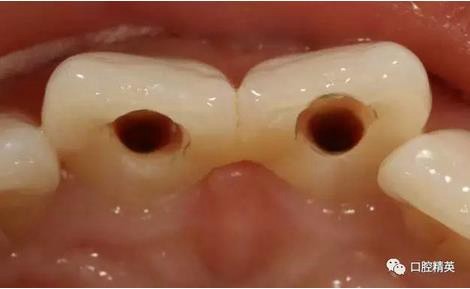

(四診)11,21唇側(cè)膿腫基本消除,叩(-),預備樁道,置入纖維樁,備牙,取模,翻制臨時冠。

術中根管治療,置人纖維樁,牙體預備,臨時冠修復

臨時冠修復

使用原始模翻制的臨時冠